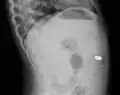

- A coin seen on lateral CXR in the esophagus

- Lateral X ray showing a 9mm battery in the intestines